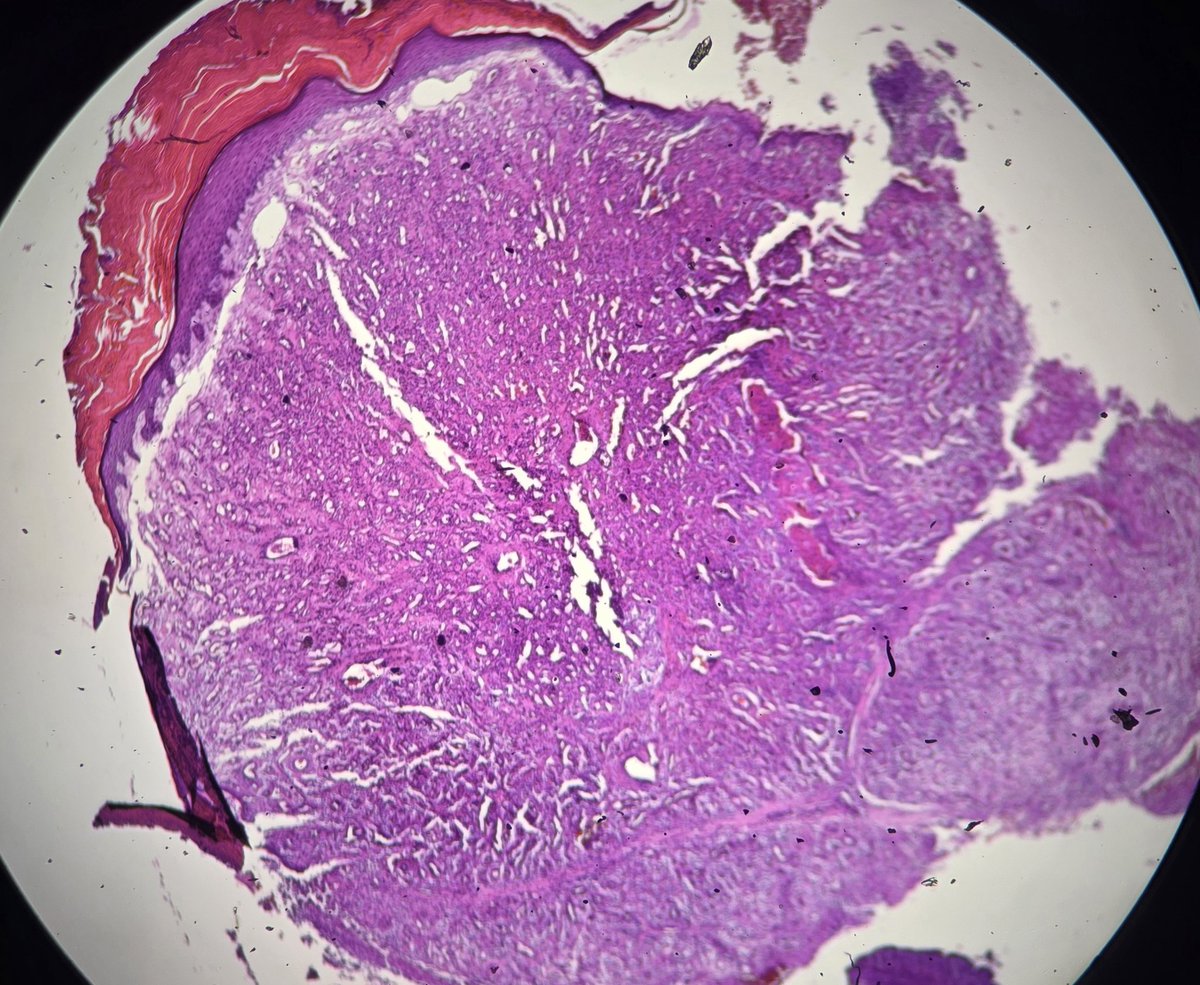

Papillary squamous cell carcinoma of cervix is a rare variant of squamous cell carcinoma of the cervix characterized by papillary architecture with fibrovascular cores and malignant squamous epithelial lining.

#pathology #gynepath #SCC #Papillary